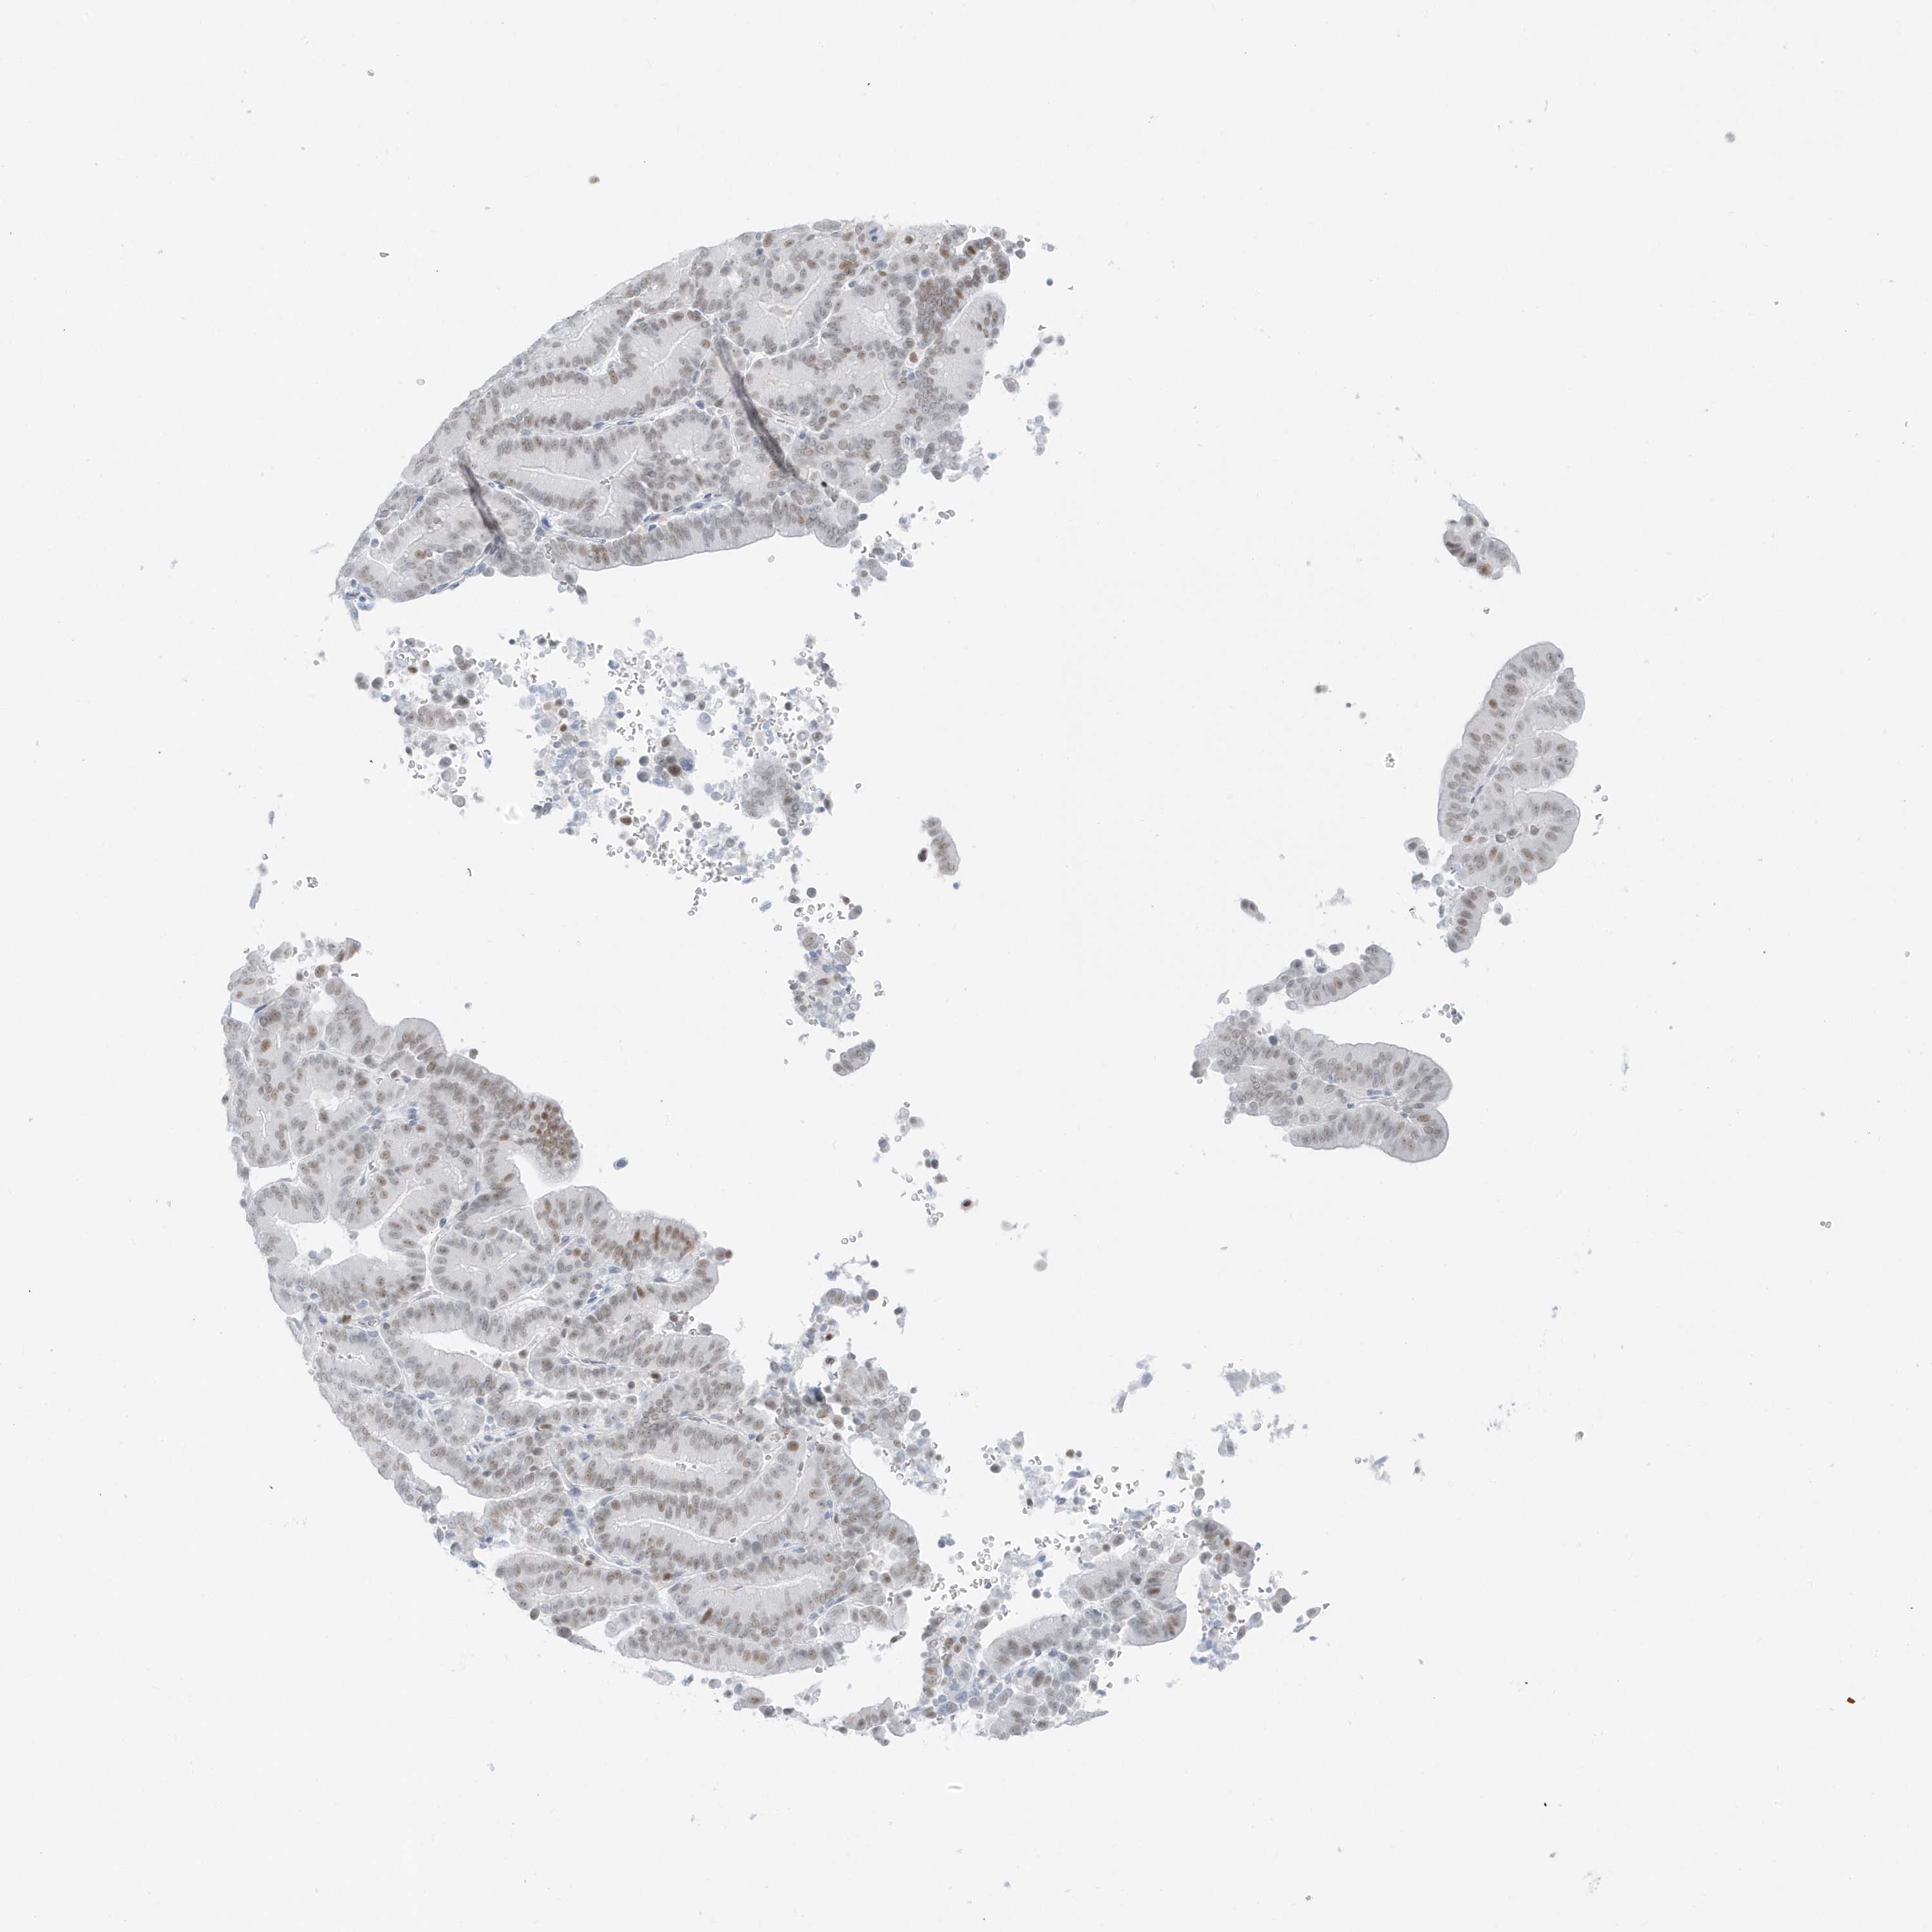

LIVER CANCER - Protein expressioni

A mouse-over function shows sample information and annotation data. Click on an image to view it in a full screen mode. Samples can be filtered based on level of antibody staining by selecting one or several of the following categories: high, medium, low and not detected. The assay and annotation is described here.

Note that samples used for immunohistochemistry by the Human Protein Atlas do not correspond to samples in the TCGA dataset.

Antibody stainingi

Antibody staining in the annotated cell types in the current human tissue is reported as not detected, low, medium, or high, based on conventional immunohistochemistry profiling in selected tissues. This score is based on the combination of the staining intensity and fraction of stained cells.

Each image is clickable and will lead to virtual microscopy that enables deeper exploration of all samples and also displays staining intensity scores, fraction scores and subcellular localization as well as patient and tissue information for each sample.

Antibody HPA029085

Staining

High

Medium

Low

Not detected

Intensity

Strong

Moderate

Weak

Negative

Quantity

>75%

75%-25%

<25%

None

Location

Nuclear

Cytoplasmic/membranous

Cytoplasmic/membranous,nuclear

Cholangiocarcinoma